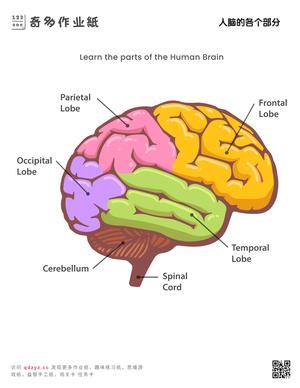

奇多作业纸生活常识系列提供幼儿通识教育资源,涵盖天气与季节认知、人体部位图解、交通安全常识、动植物百科、日常卫生习惯等核心主题。内容设计参照《3-6岁儿童学习与发展指南》科学领域目标,通过图片认知、分类游戏和问答练习三种形式实现多维度学习。常识教育是幼儿建立世界认知框架的基础环节,也是幼小衔接面试的常考内容。所有资源下载打印,适合3-7岁儿童使用。

- 掌握基本身体部位名称和功能

包括:交通安全规则(红灯停绿灯行)、卫生习惯(饭前洗手)、四季变化特征、基本身体部位名称、常见动植物辨认、简单的天气现象识别等。

通过图片闪卡、问答游戏和场景模拟三种方式效果最佳。例如用天气卡片认识晴天、雨天;用人体图谱学习身体部位;用交通标志卡开展安全教育。